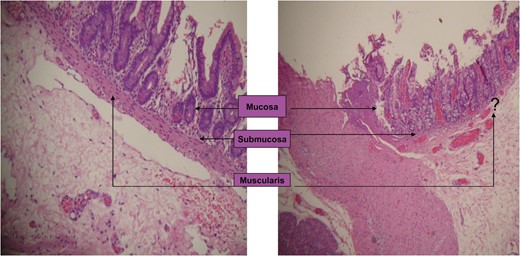

Microscopic examination showing a normal portion of duodenum with a full thickness of the wall and duodenal web lacking the muscularis propria layer.

Duodenal web occurs in 1 out of 10 000–40 000 births [3]. The failure of recanalization leaves behind a thin web with mucosa and submucosa layers only; the muscular layer is absent [3]. With a high amount of pressure proximal to the obstruction, peristalsis can cause the web to balloon distally, taking on the form of a wind sock [3, 10]. This windsock sign can be visualized on sonography, UGI series and endoscopy [10].